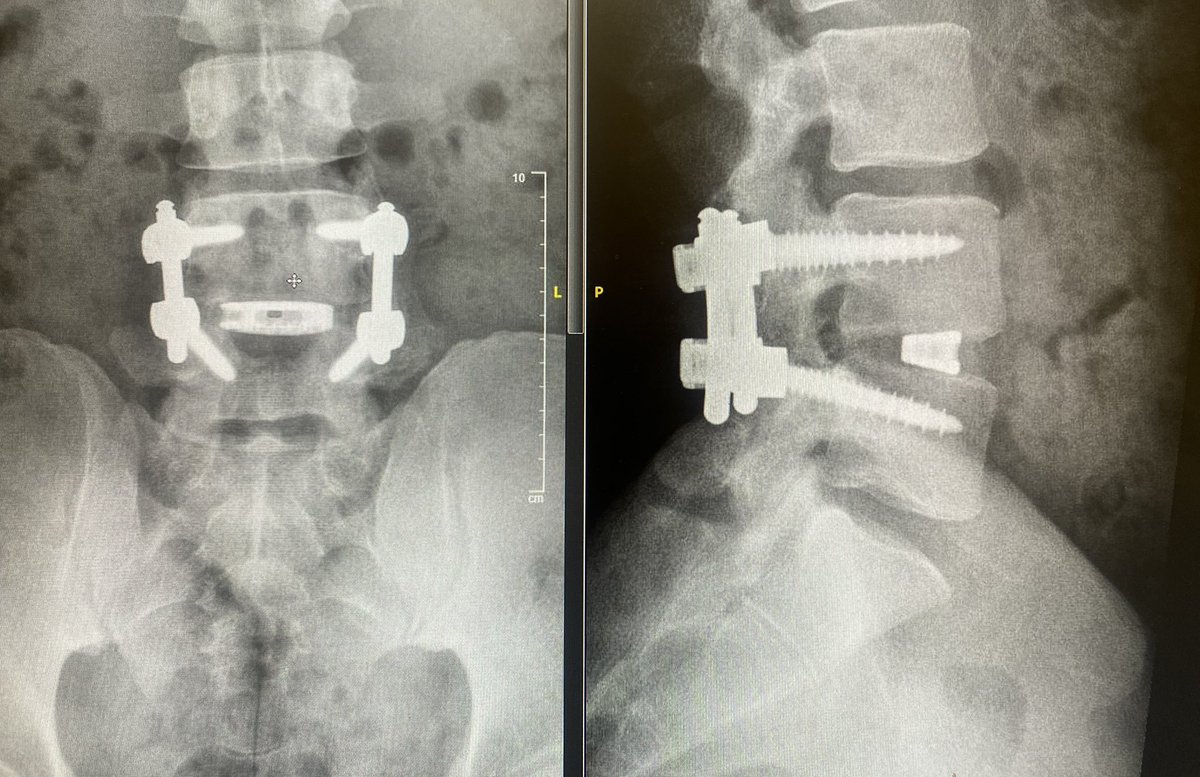

#ALIF is a mega powerful tool for reduction of #spondylolisthesis and is a surgery I am increasingly doing for appropriately indicated patients. Keys: 1. A great vascular surgeon 2. Don’t overdo it, size appropriately Mount Sinai Neurosurgery Patient permission granted

#ALIF is a mega powerful tool for reduction of #spondylolisthesis and is a surgery I am increasingly doing for appropriately indicated patients. Keys: 1. A great vascular surgeon 2. Don’t overdo it, size appropriately <a href="/MountSinaiNeuro/">Mount Sinai Neurosurgery</a>  Patient permission granted